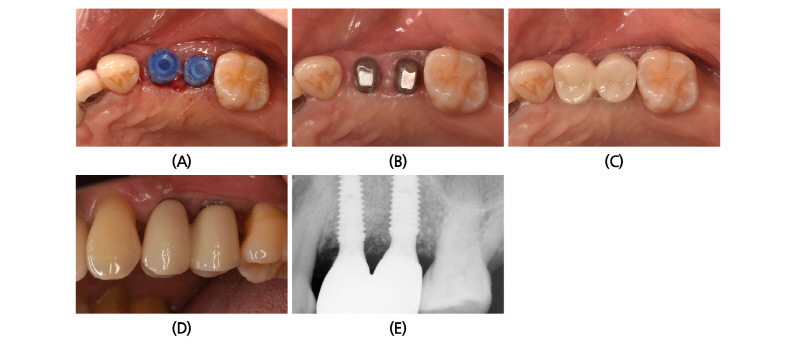

Uncovering 후에 약 3주간의 치유기간을 기다린 후 Pick Cap Impression coping을 사용하여 인상 채득과 교합인기를 채득한 후에 보철물을 제작하였다. 개별지대주를 position jig를 사용하여 장착한 후에 15분 정도의 시간 차를 두고 지대주 나사를 2번 이상 30 Ncm 이상으로 고정하고, 그 기간에는 지대주의 침하를 유도하기 위해 환자에게 Cotton Roll을 물고 있게 하였다. 그 후 전부-지르코니아 보철물을 이용하여 접촉점과 교합을 조정한 후에 영구 접착하였다(Intercem®) (Fig. 4A-4D).

보철물 접착 후 잔존 접착제의 유무를 판단하기 위해 구내 방사선 촬영을 실시하였다(Fig. 4E).